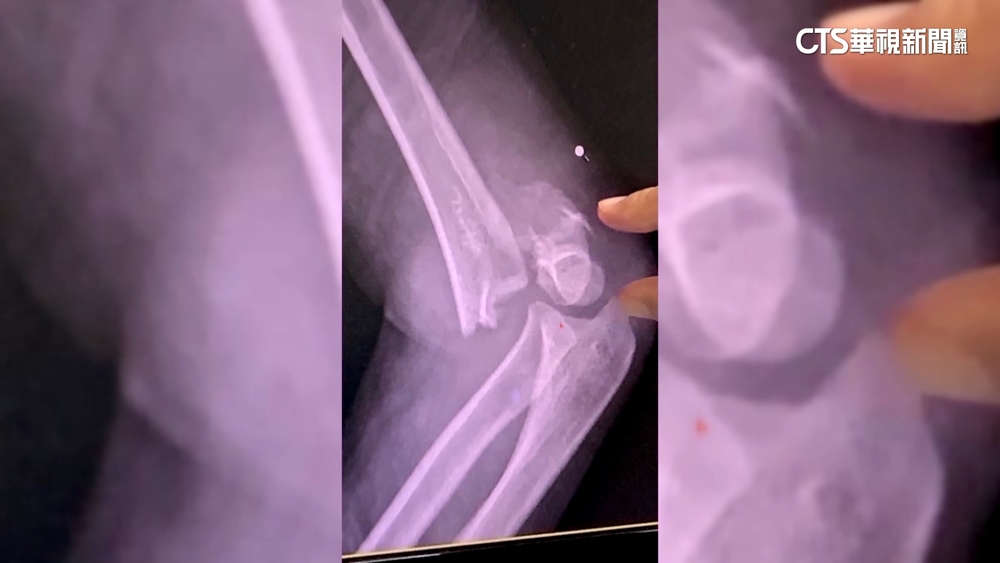

透過畫面可以看到,女童痛得哇哇大哭,家屬在一旁拼命安撫,而消防隊員獲報趕到後,緊急救援,他們先破壞手扶梯的踏板結構,接著利用器材撐開協助女童脫困,雖然她的左腳趾變形、擦傷,但送醫救治後,經過2個月的休養,狀況恢復良好。